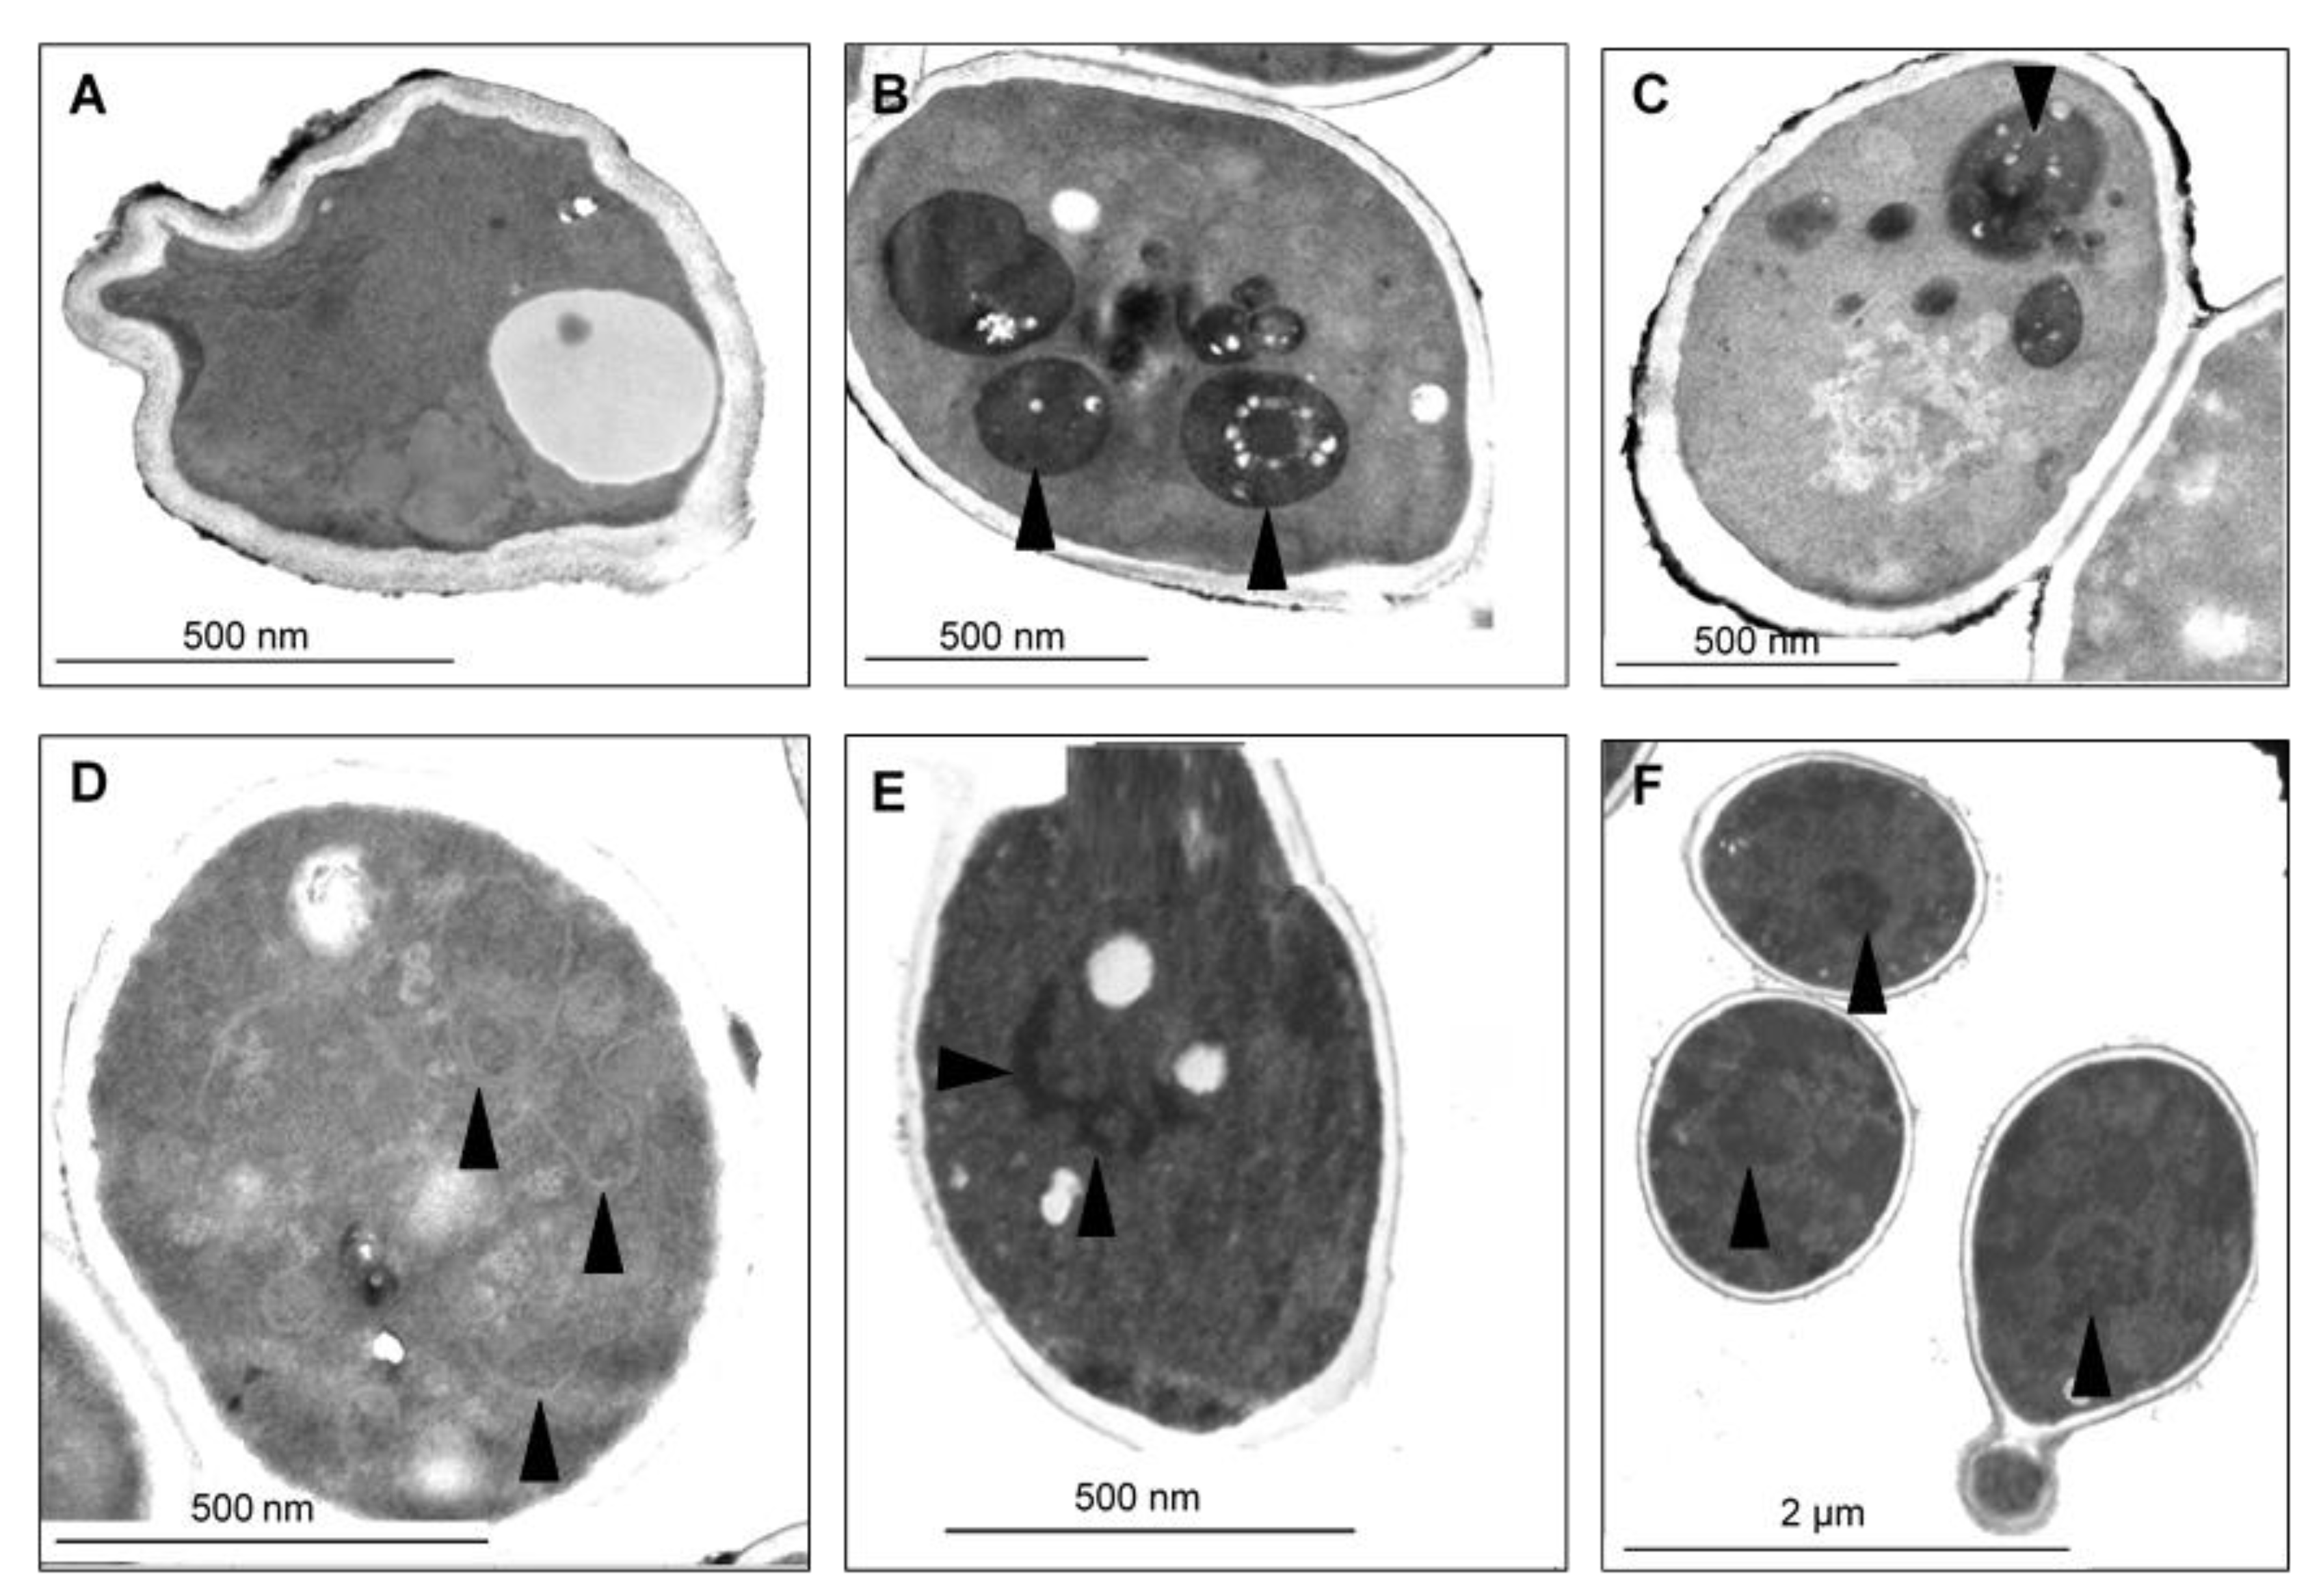

Figure 8.

TEM micrographs of C. parapsilosis SZMC 8007 treated with a sub-lethal concentration of CAPE. Both apoptotic and necrotic cell structural changes were observed in samples. (A) Nuclear chromatin margination and condensation (arrowhead) and blebs (double arrowhead) detached from the nucleus are typical apoptotic hallmarks. (B) Few necrotic cells were also present. Note membrane disintegration, obvious vacuolization, and loss of cytoplasm density. (C) Peripheral vacuole formation refers to Golgi fragmentation and cell membrane separation from the cell wall (arrowheads). Nuclear blebs (double arrowhead). (D) Nuclear condensation (arrow) and extremely large lysosomal bodies (arrowhead). Note the swollen mitochondria (double arrowheads).

Figure 9.

TEM micrographs of C. glabrata SZMC 1374 treated with a sub-lethal concentration of CAPE. (A–C) Mainly smaller necrotic signs were detected. Arrowheads denote small, mainly peripheral vacuoles typical of all samples. (B) Cell wall disintegration was also observed (double arrowhead).